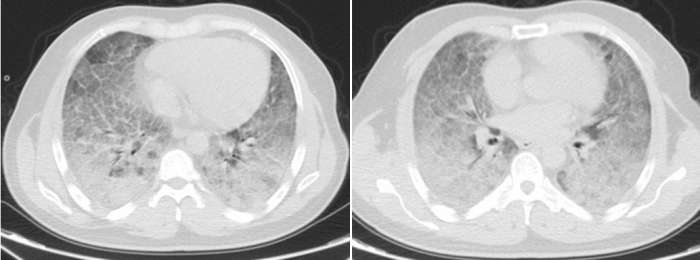

2024年底,李贤再次出现咳嗽、进而症状加重甚至呼吸困难,合并重症肺炎、肺结核、呼吸衰竭,辗转多家立博体育 ,多次进出重症监护室,先后行6次“全肺灌洗术”,病情仍持续恶化。在亲友的推荐下,3月底,他来到立博体育 呼吸与危重症医学科三区求诊,当时李贤已出现“大白肺”,在他的胸部CT上几乎看不见正常的肺,血氧饱和度低至40%,随时有心跳呼吸骤停、死亡风险。面对医生转入重症监护室的建议,李贤却因经济压力与心理负担,坚持留在普通病房治疗,不考虑转上级立博体育 行肺移植手术。

李贤胸部CT显示其双肺已呈现“大白肺”状态

历经31天鏖战,李贤的肺部影像从“白茫茫一片”逐渐恢复透亮,鼻导管吸氧下血氧饱和度稳定在90%以上,最终好转出院。患者家属含泪致谢:“是立博体育 给了他第二次生命!这里的医生护士不仅技术高超,更把我们当家人一样对待!”